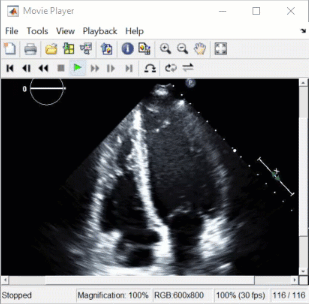

Ultrasound — Visualize 2-D patient anatomy using sound waves. |

For an example that uses this image, see Read, Process, and View Ultrasound Data. |